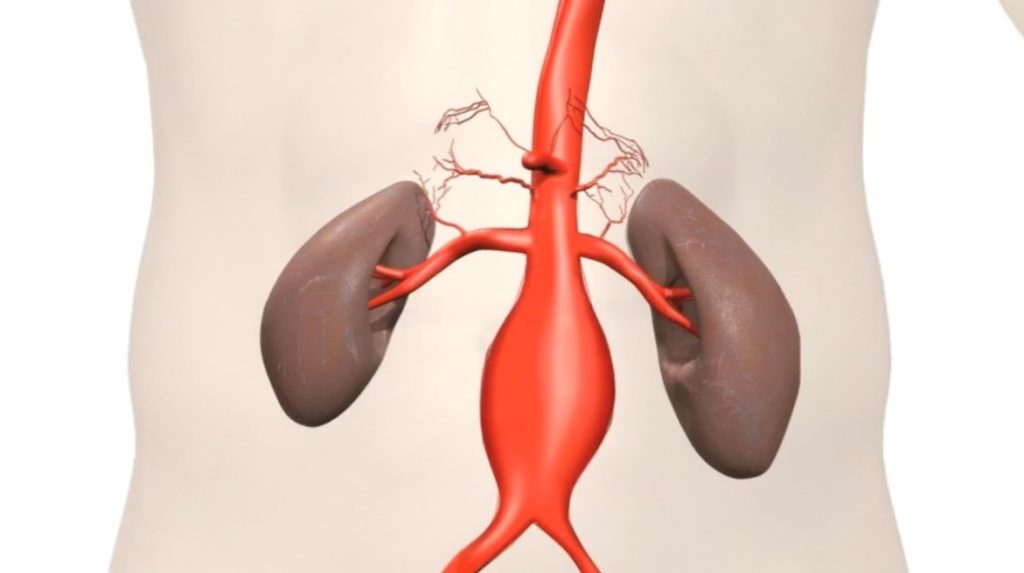

Abdominal Aorta

- AAA (Abdominal Aortic Aneurysm) Screening A vital scan that measures the diameter of the aorta—the main blood vessel in the body. This screening is highly recommended for men over 65 and anyone with a family history of aneurysms to detect any early signs of swelling.

- £150

- Ideal for: Routine screening for men 65+, smokers, or those with a family history.

- A specialist check using Doppler ultrasound to look at the blood flow to the kidneys. This screens for narrowing in the arteries, which can sometimes be an underlying cause of high blood pressure.

- £300

- Ideal for: Investigating secondary causes of high blood pressure.